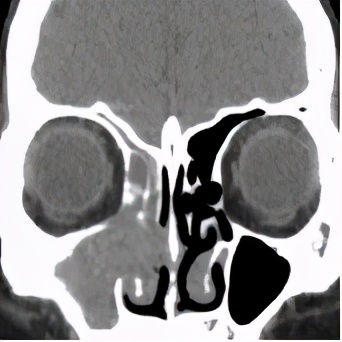

术前CT显示右侧鼻腔鼻窦密度增高,术后CT显示双侧鼻窦正常